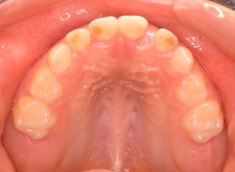

治療前

治療開始時